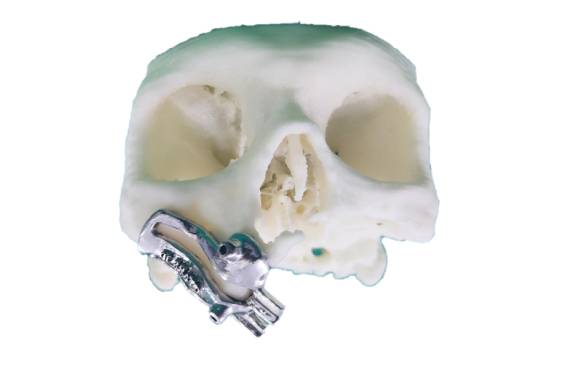

Zygoma Implant Positioning Guide

Image